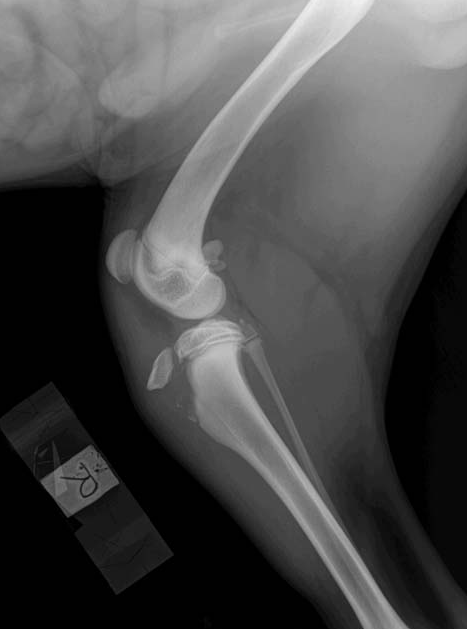

Please look below at all these x-rays from last years random friend’s injuries ( and these are without even searching as these happen all the time). If it is not a growth plate , it is a neck, back, wrist, hock, ribs or any large bones for that matter. One of the most common example is when a small piece of the knee joint splits, which end up in a 2-3000€ surgery. I do not see much point in taking such a huge risk, so don’t run adults and pups! Period!

Here is the proof! More info after the pictures!

Fractures Involving Growth Plates

Article Written by Dr. Daniel A. Degner, Board-certified Veterinary Surgeon (DACVS)

Anatomy • Dogs and cats under one year of age have growth plates, which are located near the ends of the bones of the limbs.

• The growth plates are much softer than other regions of the bones, therefore are more prone to injury.

Growth plate injury • Since most of the longitudinal growth of bones occurs up to eight months of age, growth plate injuries that occur after this point are not as devastating.

• The growth plate is a weak link in the bone construct, therefore it is more susceptible to injury.

• A Salter-Harris classification of growth plate fracture has been described in humans and seems to relate to prognosis. Type 1 has the best prognosis and type 5 having the worst.

• In pets the Salter-Harris classification also may relate to the final prognosis, but the age at which the fracture occurs tends to be a significant factor.

• The diagrams below show the different type of fractures (the blue line represents the soft growth plate tissue, the red line represents the fracture line, and the speckled red line is a crushed growth plate).

Common locations of the various Salter-Harris growth plate fractures in dogs and cats • Type1 – hip joint (slipped femoral capitis), knee (distal femur)

• Type 2 – knee (distal femur)

• Type 3 – elbow (distal humerus)

• Type 4 – elbow (distal humerus)

• Type 5 – 1. wrist or carpus (distal ulna or the distal radius less commonly), this results in an angular limb deformity); 2. ankle or hock (distal tibia)